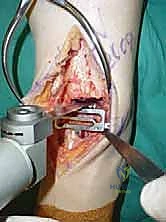

يتم إخضاع المريض لتخدير نصفي (Spinal Anesthesia) أو تخدير عام بناءً على تقييم طبيب التخدير. يتم استخدام عاصبة (Tourniquet) حول الفخذ لمنع تدفق الدم مؤقتاً، مما يوفر حقلاً جراحياً نظيفاً وخالياً من النزيف. يوضع المريض على ظهره مع رفع الساق قليلاً.

2. الشق الجراحي والنهج الأمامي (Incision & Anterior Approach)

يقوم الدكتور هطيف بعمل شق طولي دقيق في الجزء الأمامي من الكاحل، طوله حوالي 10-15 سم. يتم تشريح الأنسجة بعناية فائقة للوصول إلى المفصل.

* الحماية العصبية الوعائية: هذه هي الخطوة الأكثر حرجاً. يتم تحديد الحزمة الوعائية العصبية (الشريان الظنبوبي الأمامي والعصب الشظوي العميق) وسحبها برفق شديد لحمايتها من أي ضرر جراحي.

4. وضع أدلة القطع (Jig Placement and Alignment)

تعتمد دقة الجراحة على المحاذاة الصحيحة. يتم استخدام أجهزة توجيه متطورة (Jigs) تثبت على عظمة الساق باستخدام دبابيس معدنية. يتم التحقق من صحة الزوايا والمحاور باستخدام جهاز الأشعة السينية المباشر داخل غرفة العمليات (C-arm Fluoroscopy). يضمن الدكتور هطيف أن يكون القطع موازياً للأرض تماماً عند وقوف المريض.